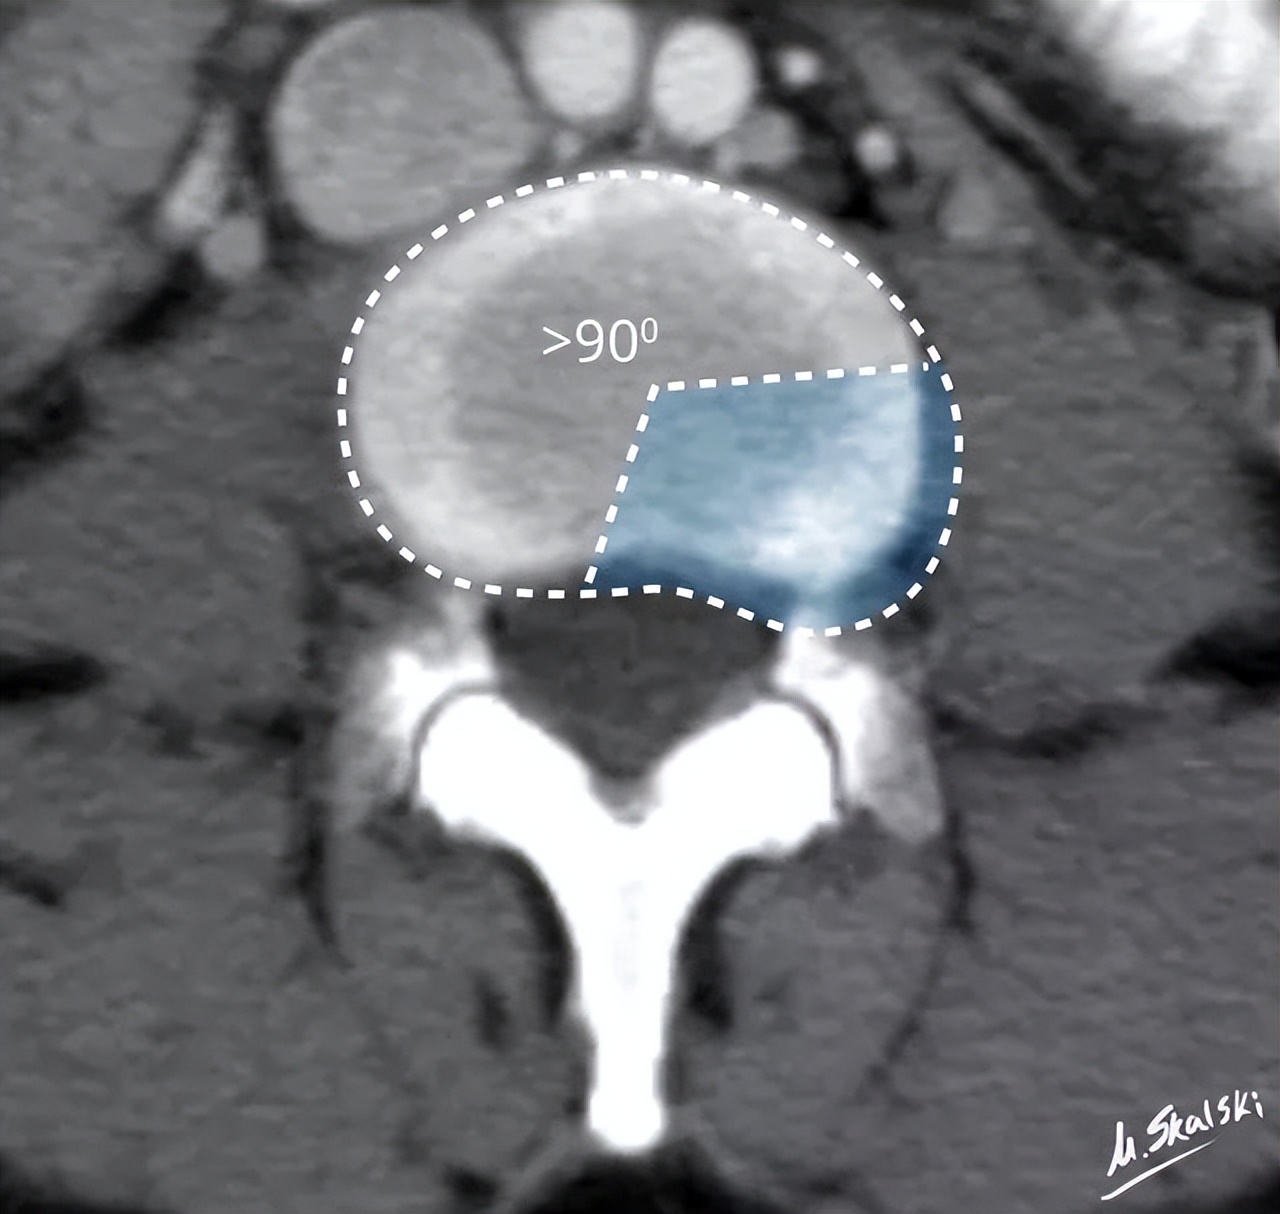

椎间盘膨出,纤维环范围超出椎体边缘

椎间盘膨出的影像学定义为:突出部分>椎间盘边缘的25%,或者突出的两边与髓核的中心的夹角>90°